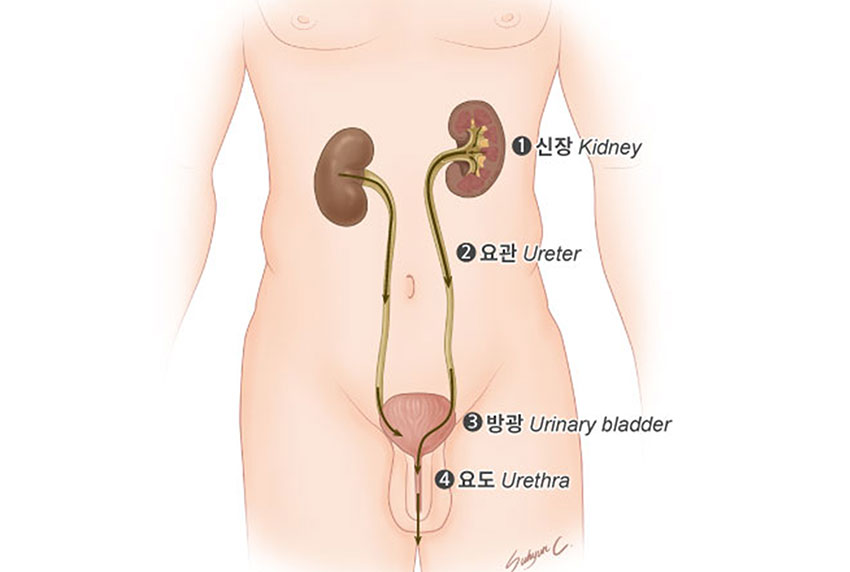

발생부위

방광은 속이 빈 주머니 모양의 근육이며 점막, 점막하조직, 근육, 장막의 4개의 층으로 이루어져 있습니다. 방광은 위로 신장에서 내려오는 요관과 연결되어 있고, 아래로는 요도와 연결되어 있습니다. 방광은 소변을 저장하고 배설하는 기능을 합니다.

<출처 국립암센터, 국가암정보센터 >